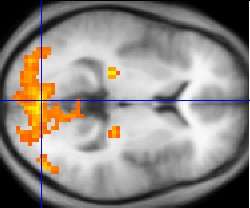

Functional MRI

Functional MRI (fMRI) is used to understand how different parts of the brain respond to external stimuli or passive activity in a resting state. Blood oxygenation level dependent (BOLD) fMRI measures the hemodynamic response to transient neural activity resulting from a change in the ratio of oxyhemoglobin and deoxyhemoglobin. Researchers use statistical methods to construct a 3D parametric map of the brain which indicates the regions of the cortex that demonstrate a significant change in activity in response to the task. fMRI has applications in behavioral and cognitive research, and in planning neurosurgery of eloquent brain areas.[29][30]

Functional MRI

Functional MRI (fMRI) measures signal changes in the brain that are due to changing neural activity. Compared to anatomical T1W imaging, the brain is scanned at lower spatial resolution but at a higher temporal resolution (typically once every 2–3 seconds). Increases in neural activity cause changes in the MR signal via T*

2 changes;[168] this mechanism is referred to as the BOLD (blood-oxygen-level dependent) effect. Increased neural activity causes an increased demand for oxygen, and the vascular system actually overcompensates for this, increasing the amount of oxygenated hemoglobin relative to deoxygenated hemoglobin. Because deoxygenated hemoglobin attenuates the MR signal, the vascular response leads to a signal increase that is related to the neural activity. The precise nature of the relationship between neural activity and the BOLD signal is a subject of current research. The BOLD effect also allows for the generation of high resolution 3D maps of the venous vasculature within neural tissue.

While BOLD signal analysis is the most common method employed for neuroscience studies in human subjects, the flexible nature of MR imaging provides means to sensitize the signal to other aspects of the blood supply. Alternative techniques employ arterial spin labeling (ASL) or weighting the MRI signal by cerebral blood flow (CBF) and cerebral blood volume (CBV). The CBV method requires injection of a class of MRI contrast agents that are now in human clinical trials. Because this method has been shown to be far more sensitive than the BOLD technique in preclinical studies, it may potentially expand the role of fMRI in clinical applications. The CBF method provides more quantitative information than the BOLD signal, albeit at a significant loss of detection sensitivity.